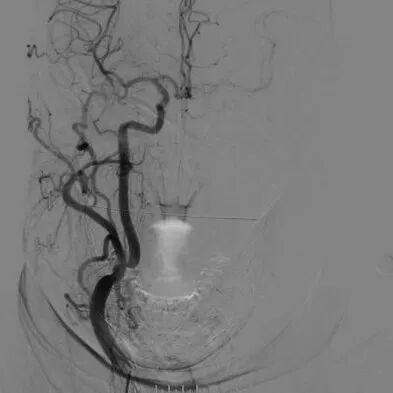

心脑联合造影

-- 左侧颈内起始部重度狭窄